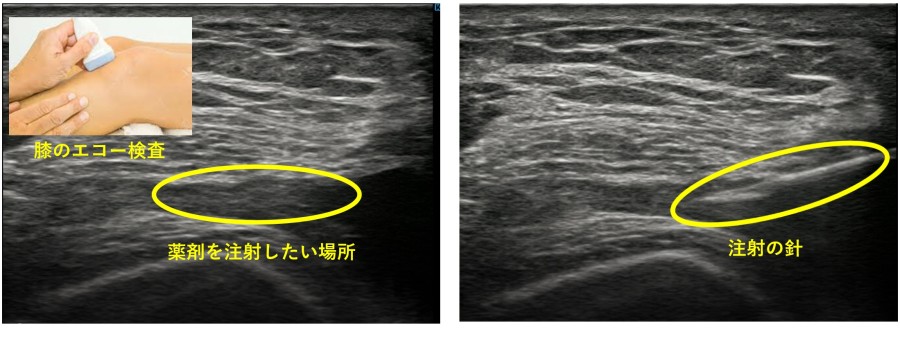

超音波検査(エコー)を導入しました。

X線検査では評価しにくい、靭帯、筋肉、腱などの組織をより正確に評価します。

また、針先を見ながら注射をすることで、より正確に患部に薬剤を投与するなど、診断だけではなく治療にも役立てています。